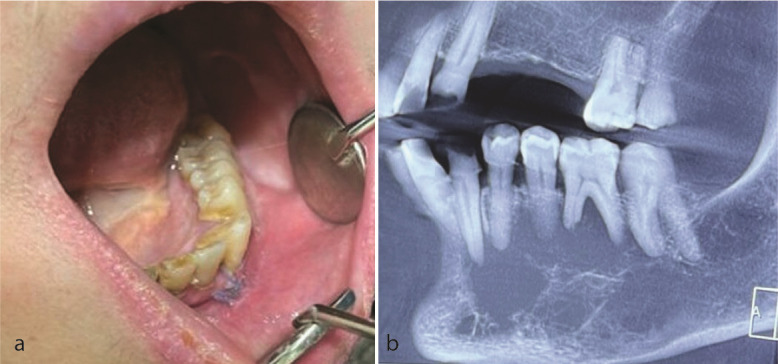

Jawbone metastatic lesions are a diagnostic challenge because of their rarity and variable clinical, radiographic, and histopathologic characteristics. This paper presents a 57-year-old female with a chief complaint of lower face swelling. Cone beam computed tomography (CBCT) showed a multilocular radiolucency with right angle septa in the left mandibular area with cortical destruction. She had a history of right breast cancer about six years ago. Histopathologic examination revealed sheets of malignant small round cells. Immunohistochemistry (IHC) was only positive for cytokeratin (CK) and GATA3. CA15-3 tumor marker was higher than the normal range. Based on the aforementioned data, the diagnosis of metastatic breast carcinoma was performed. The whole-body and computed tomography (CT) scan showed just involvement in the left mandibular area. The radiographic appearance of metastatic lesions might be misleading, and microscopic sections might be poorly differentiated, therefore, a precise past medical history, IHC staining, and tumor markers are valuable issues in diagnosing oral cavity metastasis.